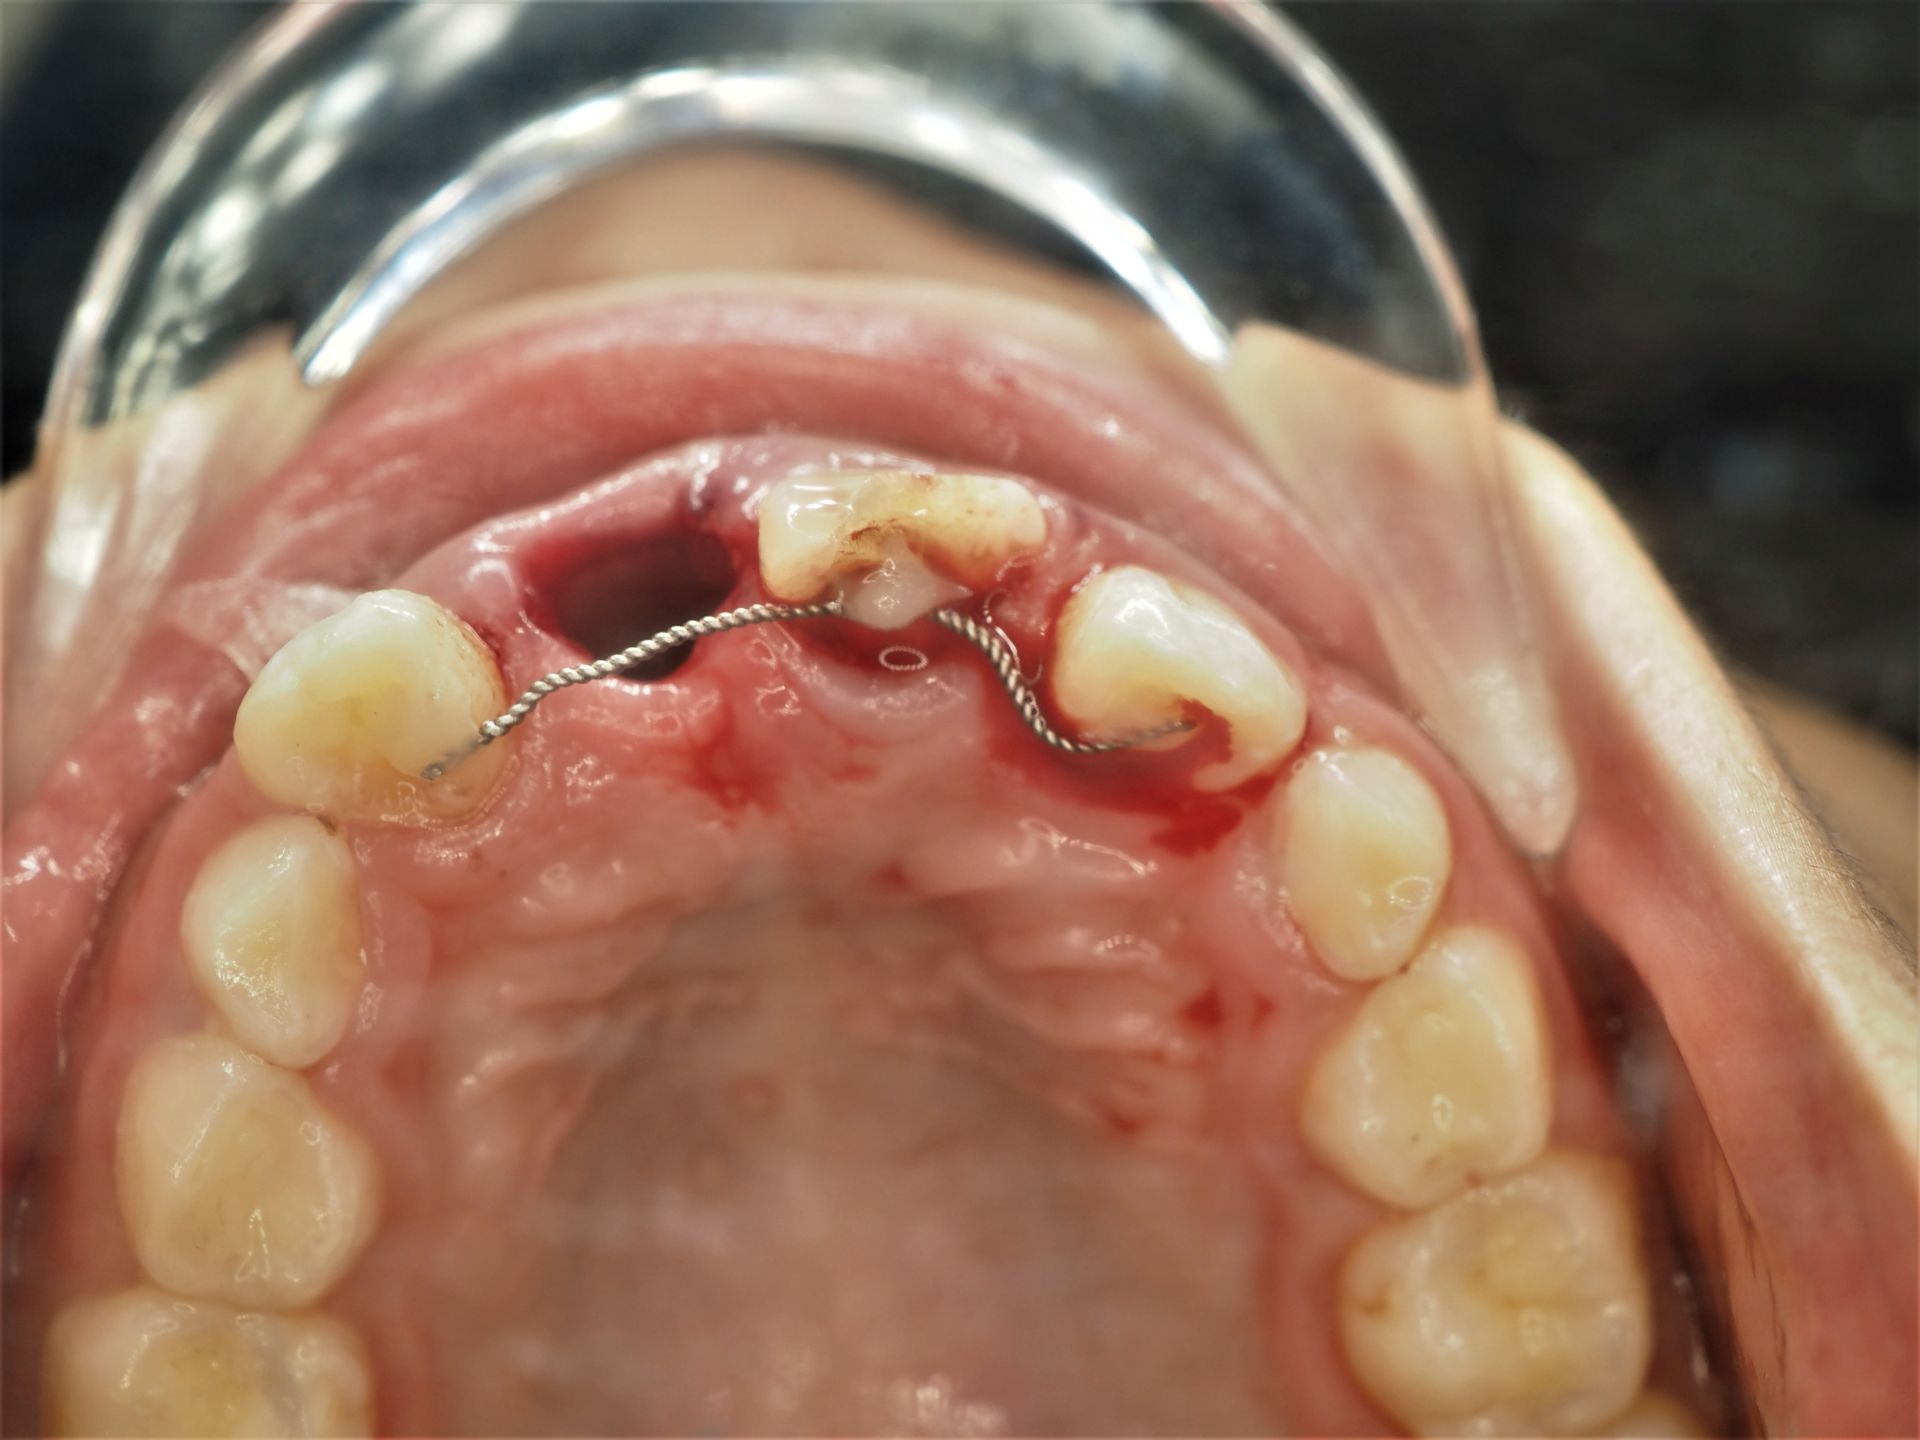

A knocked-out tooth is a tooth that has been completely dislodged from its socket due to injury. Immediate dental care is crucial to improve the chances of saving the tooth.

We may reposition the tooth and secure it with a dental splint to stabilise it while the surrounding tissues heal.

Still in socket: Splint (stabilize using adjacent teeth)

Knocked out: CAN BE SAVED. Protect tissue at tooth root

(Can rinse but must not scrape or wipe tooth root).

Reinsert (best) or place below tongue or in milk/saliva and see dentist ASAP (ideal: within 30min)